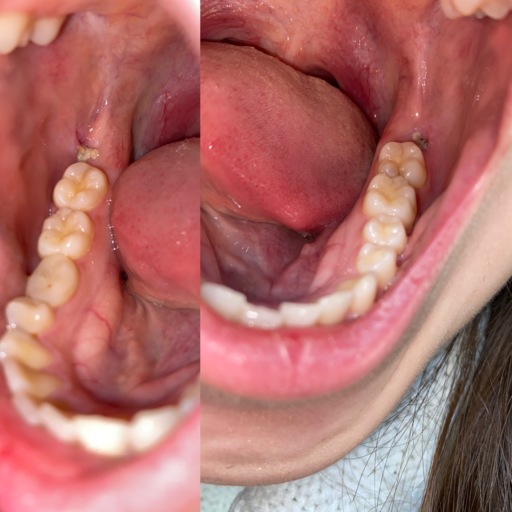

\\\"My son is 12 years old. He has two impact canines. Pulled his baby ones, put him in braces due to over crowding bottom and over bite. Now we need to make the hard decision to pull his adult lateral teeth to make room for the canine to come down. The oral surgent is suggesting this due to the position of the canine. I wish we can save them all, but he is saying it\\\'s a big surgery, it could cause damage to some roots of heathy teeth, and there\\\'s a good possibility they won\\\'t come down. The canines are lying vertical with the tips petruding between the front teeth and the lateral. He says by pulling the teeth they will easily come down with the least amount of surgery and the best outcome. What do you think? There\\\'s nothing like having your own teeth , but is the surgery worth the risk or should I just pull the laterals?